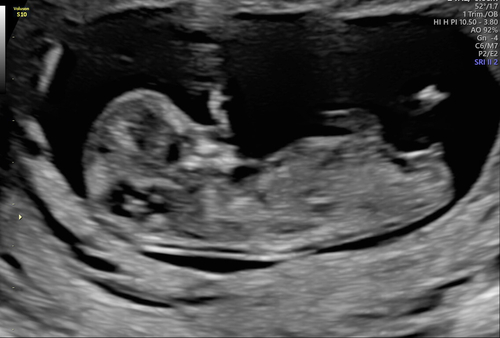

Iemand een idee? 12+3 😄

Hier nog een foto! 😊